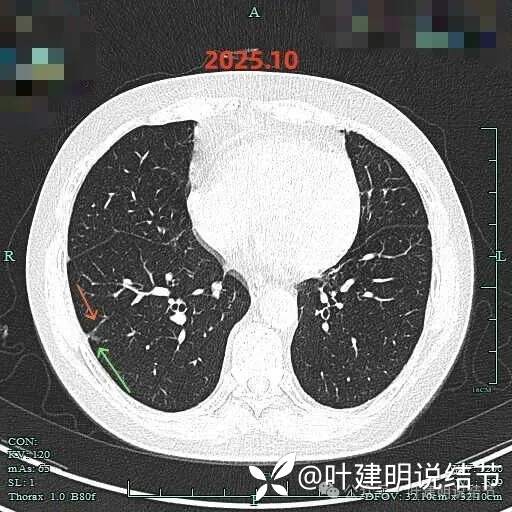

再来看2025年10月连续层面的影像:

病灶出现,有磨玻璃成分,有血管进入与穿行,血管略有增粗。

混合密度,实性成分明显,微小血管进入明显,整体轮廓清楚,瘤肺边界清楚。

边缘有少许毛刺,实性部分密度较高,牵拉胸膜,边缘少许磨玻璃成分。

边缘区域有磨玻璃成分,实性部分密度主,紧贴胸膜。

边缘淡磨,血管走向病灶。

右上实性结节表面光滑,较圆,次病灶似卫星灶,密度过高,没有显著进展。